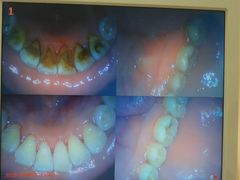

• 赫尔森口腔·牙齿种植修复

• -赫尔森口腔·牙齿种植修复

dontlikeapple | 18-06-12